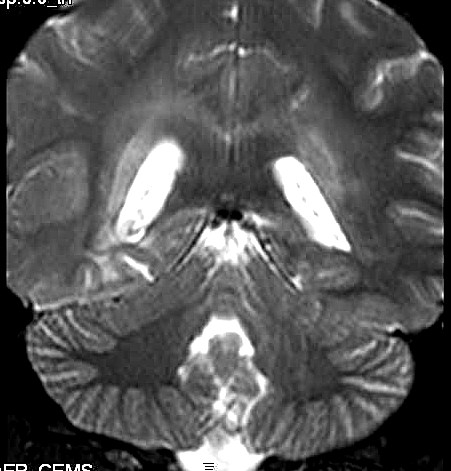

| Fem. 17a. |

| Nódulo sólido homogêneo preenchendo o III ventrículo, com limites precisos, com hipossinal em T1 e hipersinal em T2 e FLAIR, que se impregna por contraste paramagnético. Lesão menor implantada no assoalho do IV ventrículo provavelmente representa disseminação por via liquórica. |

| F. 17a. Tumor teratóide rabdóide atípico de III ventrículo. RM | HE | VIM, GFAP | HHF35, desmina, 1A4 | AE1AE3, EMA |